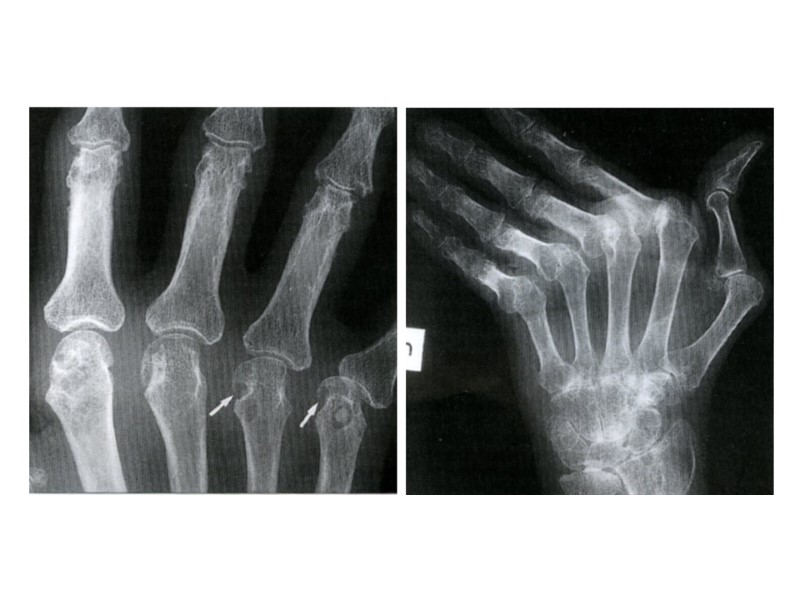

Рентгенограмма пальцев кисти Остеолиз фаланг пальцев

Рентгенограмма локтевого сустава Остеолиз суставных концов